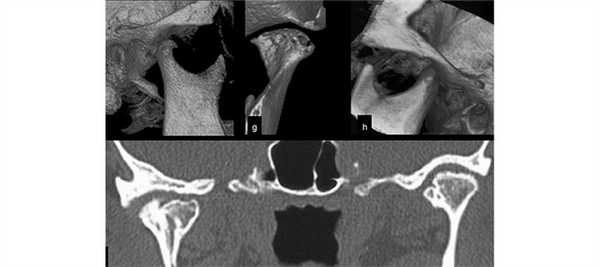

Компьютерная томография височно-нижнечелюстного сустава

КТ ВНЧС представляет собой неинвазивный метод диагностики, который основан на рентгеновском излучении. Характеризуется высоким уровнем информативности и небольшой дозой облучения, но проходить это обследование можно строго по назначению лечащего врача.

Патологии ВНЧС характеризуются нехарактерными симптомами, что усложняет процесс диагностики заболеваний. Пациент может испытывать повышенную чувствительность зубного ряда, боли в голове и нетипичную пульсацию в висках, что может указывать на целый ряд проблем. Все это может стать следствием некорректной диагностики и неправильного лечения. Характерный пример – это удаление зуба при непонятных причинах его сильной чувствительности. Чтобы этого избежать, используется компьютерная томография ВНЧС, которая позволяет дать максимально точную картину исследуемых участков.

КТ ВНЧС – что показывает обследование?

При проведении КТ, предполагаемая патология или дефект становятся хорошо видны на мониторе компьютера. Изображение может быть получено в нескольких проекциях – аксиальной, фронтальной или сагиттальной.

Полученный снимок может определить следующие виды отклонений:

- Изменение размеров суставной щели.

- Отклонения суставного диска.

- Изменение костных структур.

- Наличие новообразований.

- Смещение головок сустава.